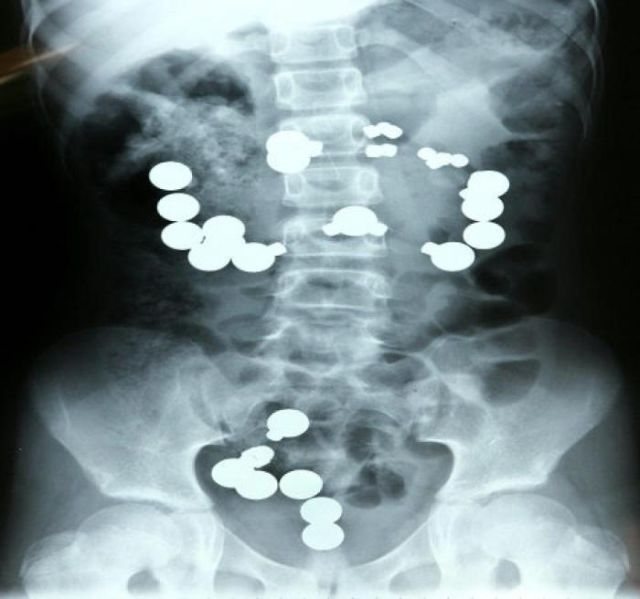

These x-rays will make you wonder how this could ever have happened in the first place.